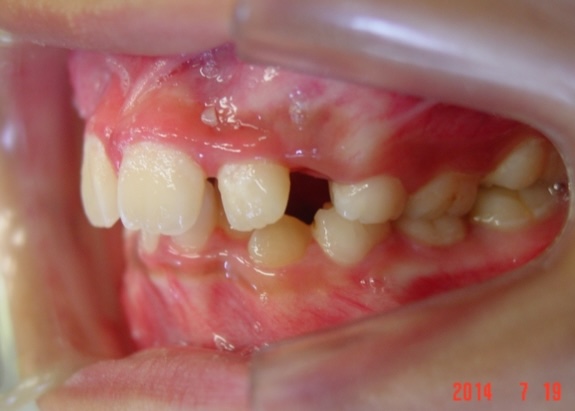

矯正前